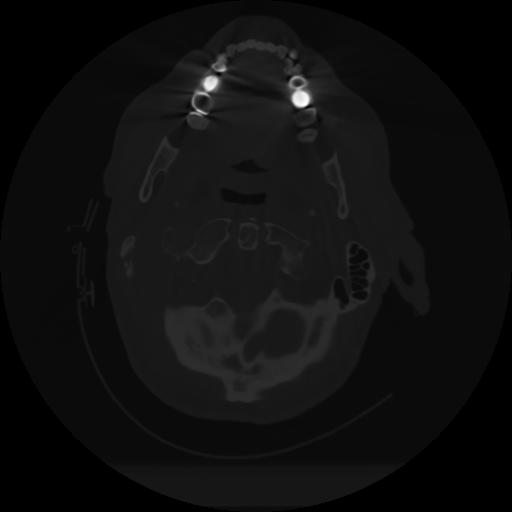

12 P.BLANDAS,,Vol,0.5,P.BLANDAS,,